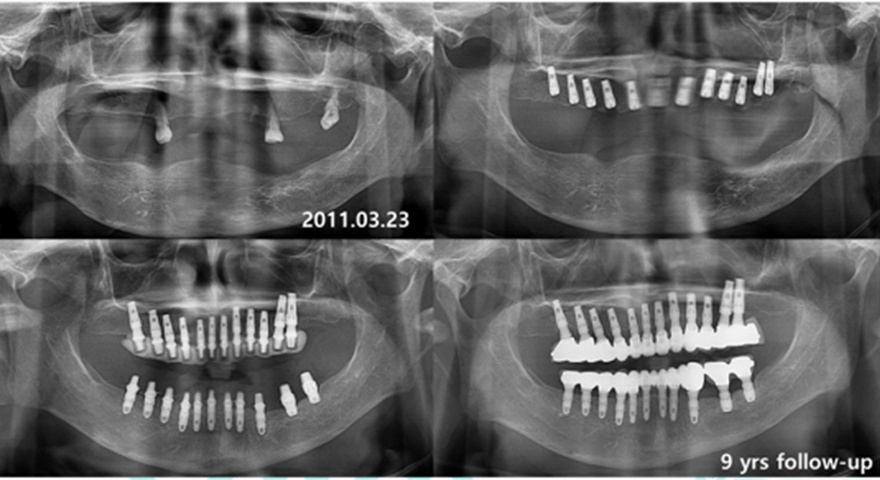

Клінічні випадки:

Одночасне встановлення короткого імплантату INNO

Фото до операції

Передопераційний панорамний знімок

віддалені результати встановлленя короткого імплантату INNO Sub. Short

дані спостережень 8-10 років